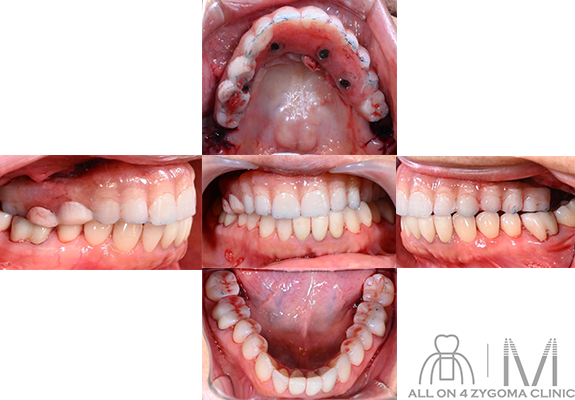

最終補綴物セット後の

口腔内所見

最終補綴物セット後の写真。上顎の最終補綴物の2┴25相当部の口蓋側に3つのアクセスホール、5┘にアクセスホールを1つ認め、オールオン4である事が確認出来る。上顎は顔貌の正中と合わせているため、下顎の正中とズレている。Angle分類は右がⅢ級、左がⅠ級関係となっている。